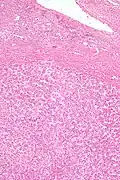

Pathologic diagnosis

Hepatic adenomas are, typically, well-circumscribed nodules that consist of sheets of hepatocytes with a bubbly vacuolated cytoplasm. The hepatocytes are on a regular reticulin scaffold and less or equal to three cell thick.

The histologic diagnosis of hepatic adenomas can be aided by reticulin staining. In hepatic adenomas, the reticulin scaffold is preserved and hepatocytes do not form layers of four or more hepatocytes, as is seen in hepatocellular carcinoma.

Cells resemble normal hepatocytes and are traversed by blood vessels but lack portal tracts or central veins.

Micrograph of hepatic adenoma. H&E stain

Micrograph of hepatic adenoma. Reticulin stain